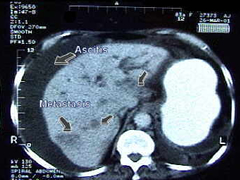

Tomografía axial de paciente con adenocarcinoma gástrico avanzado:

Se observa ascitis y metástasis hepáticas., lo que significa que dicho cáncer ya esta diseminado, encontrándose en fase muy avanzada.